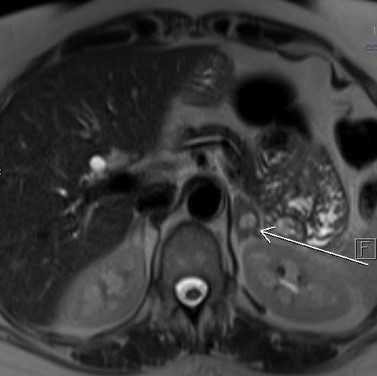

МРТ почек и надпочечников в аксиальной плоскости. Левый надпочечник увеличен в размерах за счет наличия кистозно-солидного образования, неправильно овальной формы

Почки имеют нормальную форму и положение. Толщина почечной паренхимы и кортико-медуллярная дифференцировка сохранены. Паренхима почек однородная. Чашечно-лоханочная система и мочеточники не расширены. Паранефральная жировая клетчатка не изменена, без признаков отека.